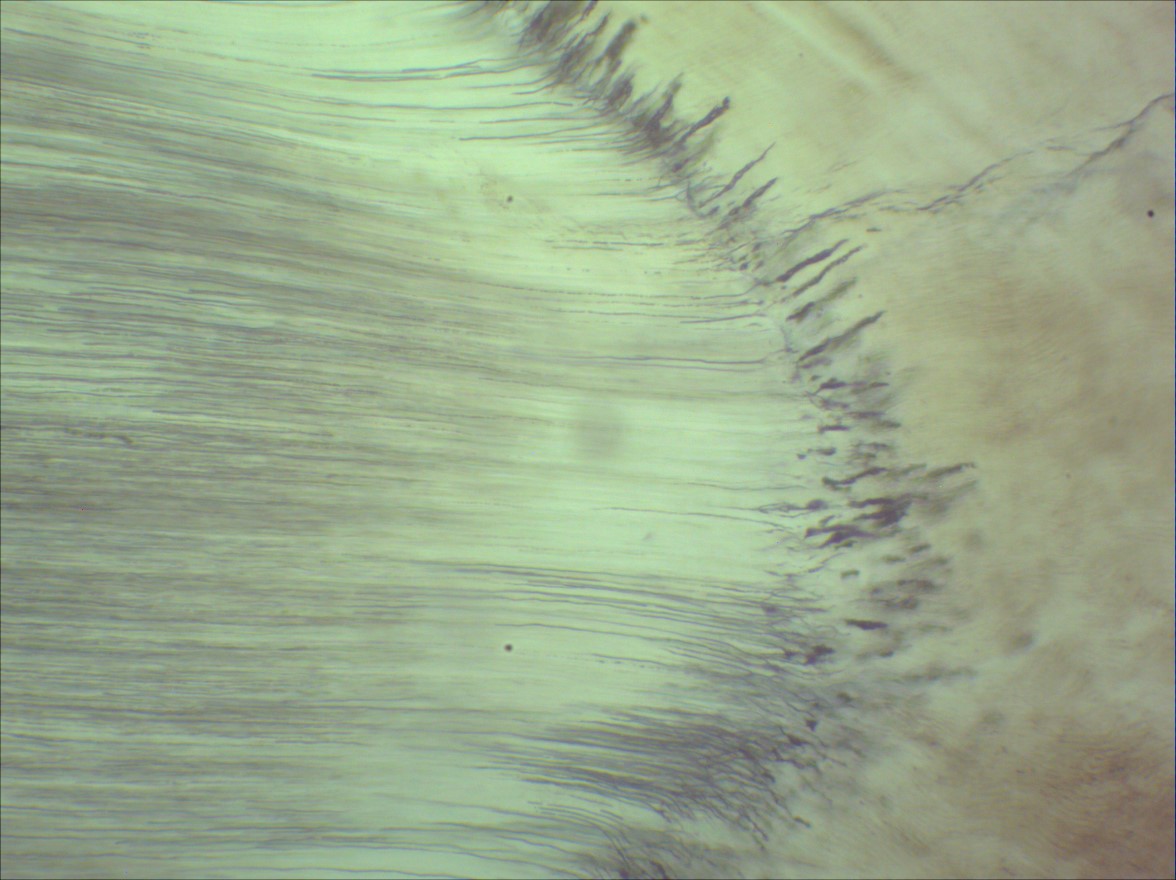

Enamel spindles were stained by eosin. Download Scientific Diagram